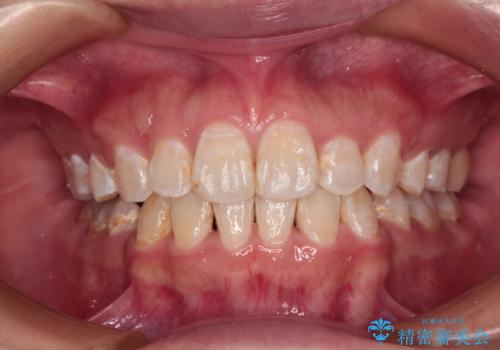

正中のズレと飛び出した前歯を改善 メタルブラケットでの抜歯矯正

- 飛び出した上顎前歯と正中のズレを気にして来院された患者様です。

上顎正中が右側にずれていたので、むし歯が酷く抜歯が必要な左側臼歯を抜歯して正中を改善することとしました。

左下には新しいセラミックのブリッジが装着されていたため、ブリッジを壊さずに改善できるところまで咬み合わせを改善していくこととしました。

右上小臼歯は銀歯が装着されており、ワイヤー矯正の装置が装着できないため、事前に仮歯に変えてから矯正治療を行い、その後オールセラミッククラウンにて補綴治療を行いました。